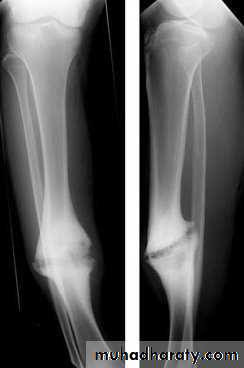

Delayed union and non union :When the fracture takes more time than expected to unite then it is delayed union

When the fracture fail to unite . For diagnosis of non union , 6 months of follow up should pass without clinical and\or radiological signs of union.

diagnosis

Delayed union : fracture tenderness persist , fracture line in the xray with very little or no callus

Non union : pain diminished , movement in the fracture site (pseudarthrosis or pseudojoint ) , xray show atrophic or hypertrophic bone ends

Treatment :

Delayed union : look for and treat the cause .Non union : treated mainly by surgical fixation with bone graft ( in Atrophic non union or without bone graft in cased of hypertrophic

Non union.

Malunion:

When the fragments join in an unsatisfactory position (unacceptable angulation, rotation or shortening) the

fracture is said to be malunited.

Causes are failure to reduce a fracture adequately, failure to hold reduction while healing proceeds

Treatment of malunited fracture:

In adults, Angulation of more than 10–15 degrees in a long bone or a noticeable rotational deformity may need correction by re- manipulation, or by osteotomy and fixation .In children, angular deformities near the bone ends (and especially if the deformity is in the same plane as that of movement of the nearby joint) will usually remodel with time; rotational deformities will not

Shortening malunion may be treated by bone lengthening procedure.